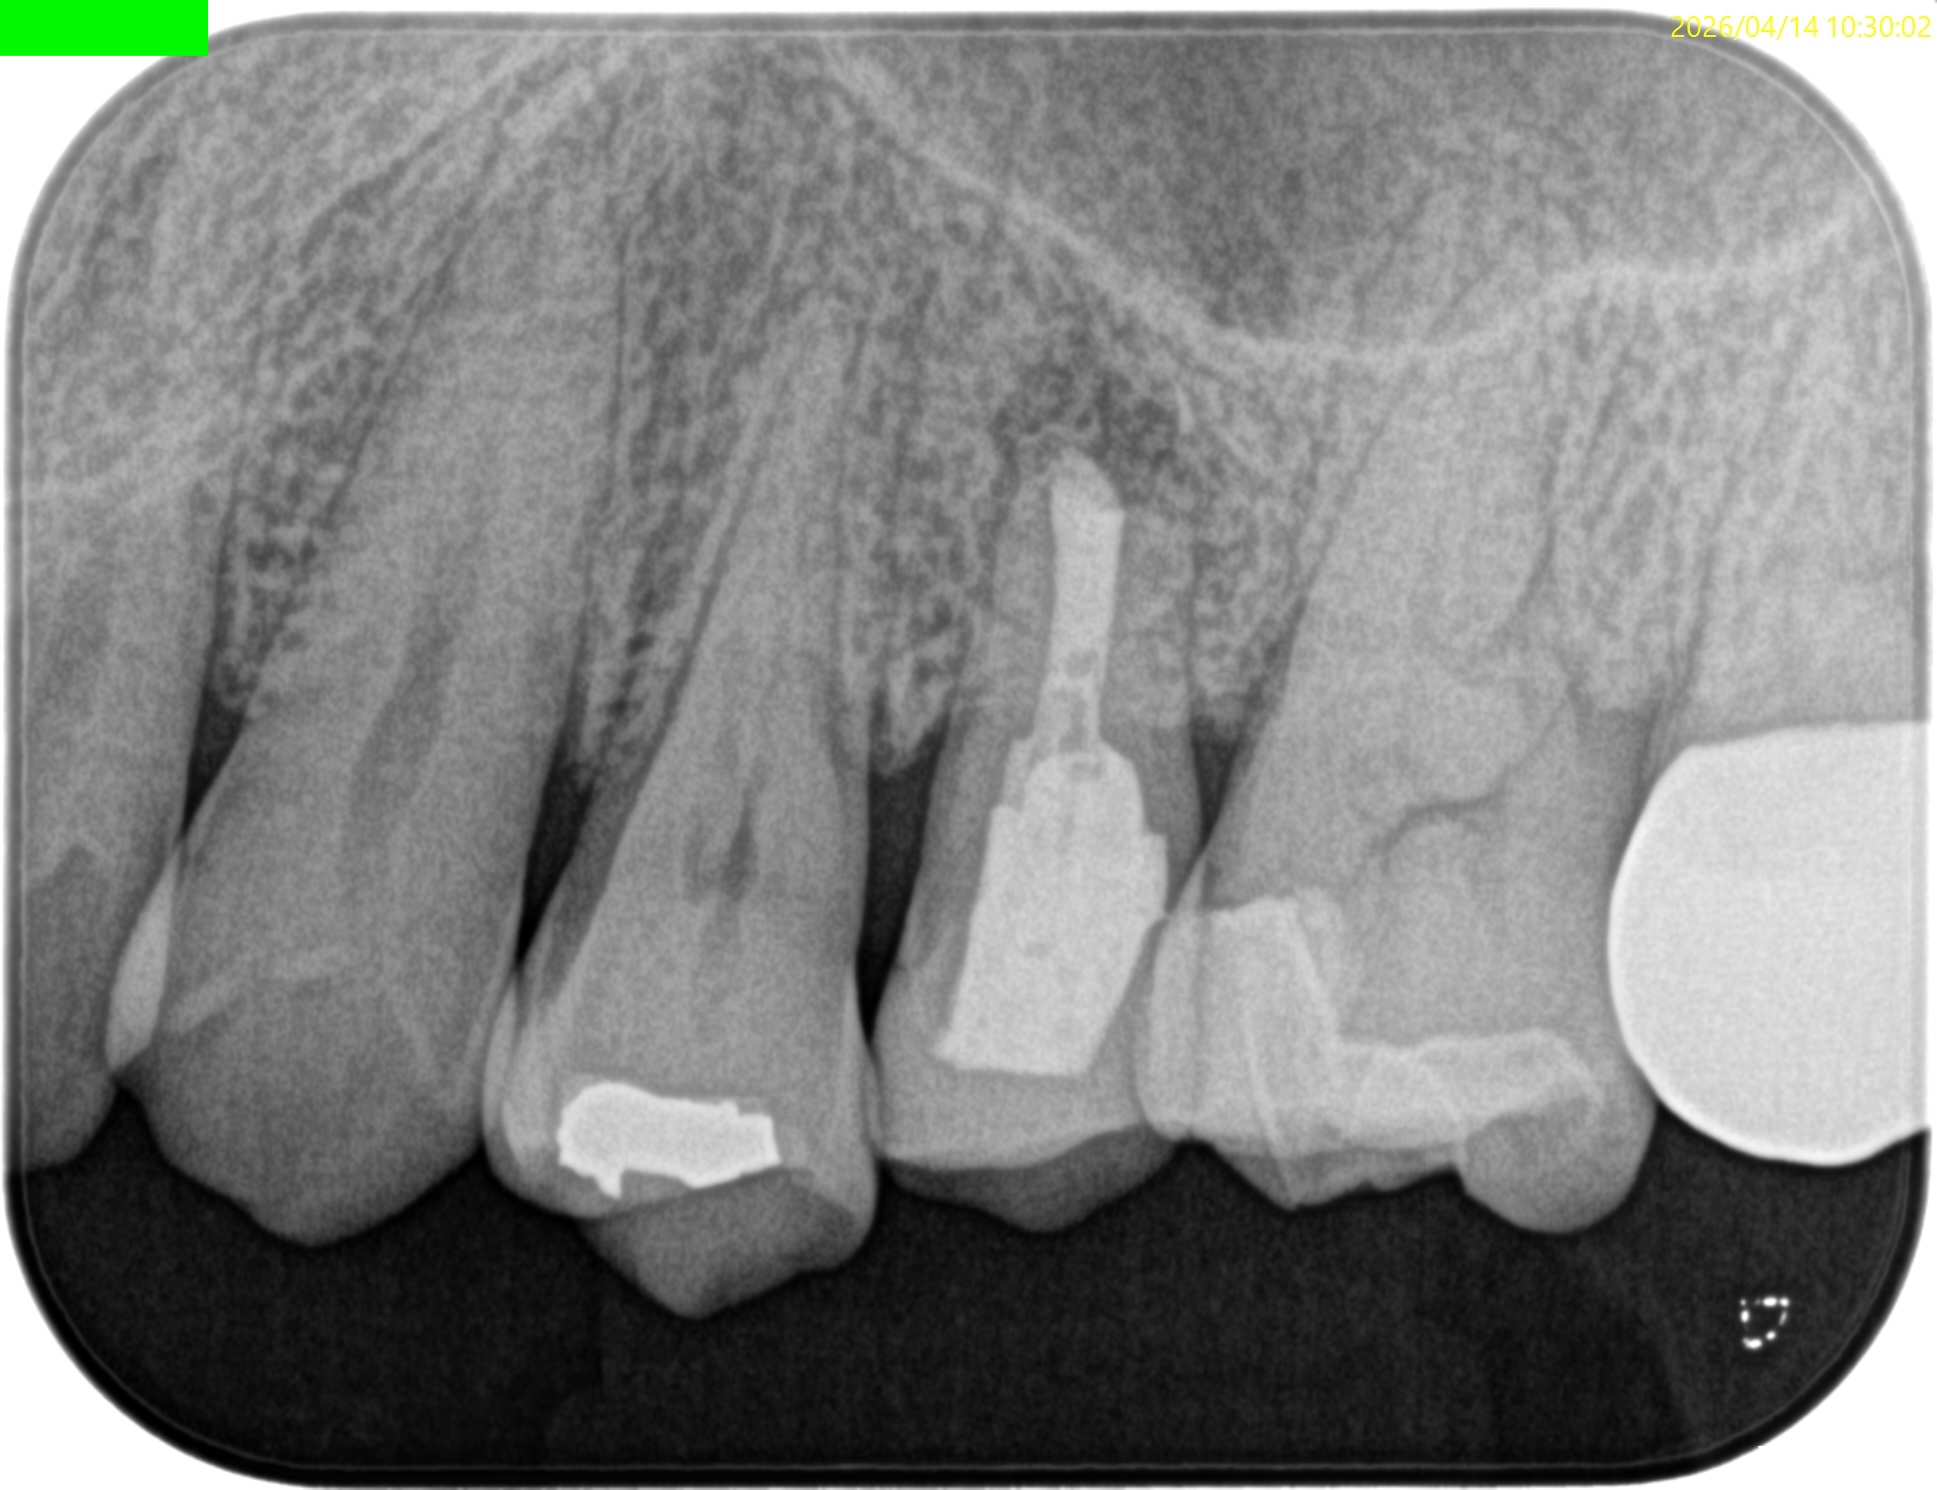

Pre-op Endo test(2026.4.6)

臨床症状はないが…

上顎洞炎は治癒したままだが、Lid TechniqueのLidごと材料が外れてしまっている。

術後にPA, CBCTを撮影した。